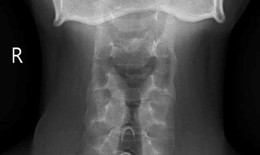

Cứu sống bệnh nhân gãy khung chậu kiểu 'gió thổi' hiếm gặp sau tai nạn xe container

Camera bệnh viện - 07/10/2025 10:12SKĐS - Sau va chạm mạnh với xe container, cô gái trẻ 24 tuổi rơi vào tình trạng nguy kịch, đa chấn thương, gãy khung chậu kiểu 'gió thổi' cực kỳ nguy hiểm. Bệnh viện Quân y 175 đã kích hoạt báo động đỏ liên chuyên khoa, phẫu thuật xuyên đêm cứu sống bệnh nhân.